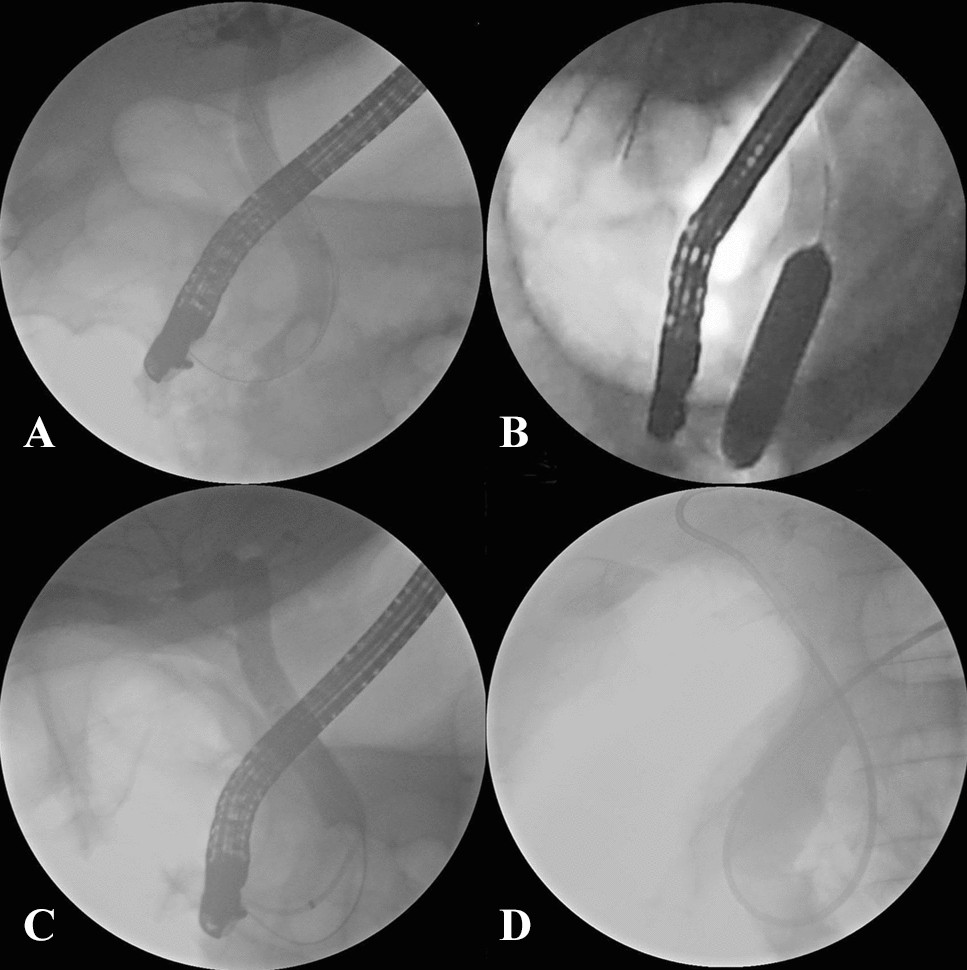

Figure 3

Fluoroscopic view of removal of CBD stones. (A) Cholangiogram demonstrating CBD stone; (B) a balloon inflated across the papilla over the guidewire; (C) the cholangiogram following complete stone removal showed no residual filling defect in CBD; (D) the placement of a nasobiliary drainage tube.